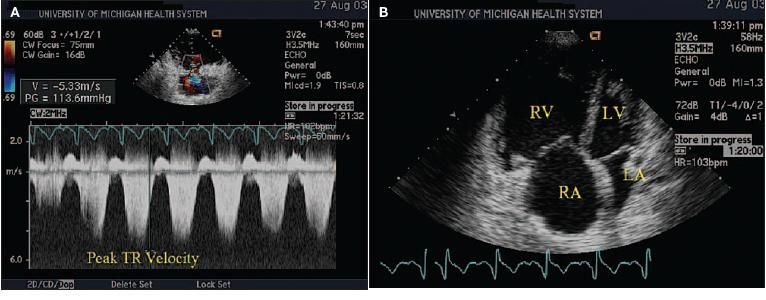

Echocardiography not only assists the diagnosis of PH but also helps determine the cause, especially if the PH is secondary to cardiac disease, such as valve disease, congenital heart disease, atrial or ventricular septal defect, or LV failure. The systolic pressure in the pulmonary artery often can be estimated by continuous-wave Doppler echocardiography through analysis of tricuspid regurgitant peak flow velocity (Figure 5).

Figure 5 – Echocardiographic and Doppler evaluations for pulmonary hypertension (PH) and right ventricular dysfunction are shown here. The tricuspid regurgitation jet with Doppler ultrasound is used to evaluate pulmonary arterial systolic pressure (PAsP) (A). PAsP equals the right atrial pressure (usually estimated as 10 mm Hg) plus the systolic pressure gradient between the right ventricle and right atrium (ΔP × 43 tricuspid regurgitation flow velocity2) (PAsP = RA + 4v2). Normal is 30 mm Hg or less. The apical 4-chamber view of the heart is from a patient with severe PH (B). Note the very enlarged right ventricle on the left side of the image. (RA, right atrium; RV, right ventricle; LA, left atrium; LV, left ventricle.)

The pulmonary acceleration time is a more accurate measurement of the systolic pressure in the pulmonary artery, but it is technically more difficult to obtain and is infrequently reported.21 The size of the right atrium and the right ventricle can be measured, and the contractile state of the right ventricle can be estimated. The addition of saline contrast to enhance the study can help assess the possibility of an intracardiac right-to-left shunt and should always be part of the patient's evaluation.